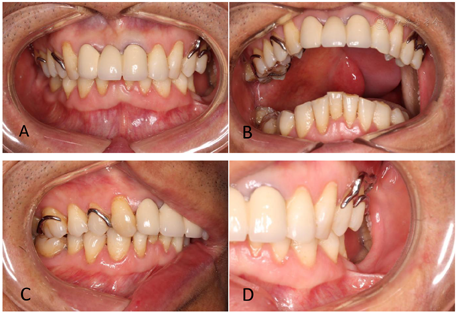

颌面部基本对称,开口约3横指,口内13~17缺失,缺牙区牙槽骨、上颌骨缺失,右侧硬腭缺失,右侧软腭缺失。右颊、右腭舌弓处有手术瘢痕挛缩。前牙深覆牙合深覆盖,后牙有不同程度磨耗。构音不清,饮水时鼻漏(图7)。病理结果提示:(右上腭)浸润性中分化鳞癌。

治疗计划:拟行上颌阻塞器式活动义齿修复。治疗过程:(1)牙体预备,制备12~26舌侧导平面和小连接体空间,制备24、25和25、26和26、27间隙卡位置。(2)制取初次印模(同病例一)。(3)试支架确定颌位关系,制取咽腔功能式印模(同病例一)。(4)试戴。(5)充胶戴牙(图8)。

术后效果见图9,患者右侧软硬组织得以恢复,构音清晰度明显提高,饮水无鼻漏。

术后5年肿瘤复发,行二次手术,术后旧义齿松动,构音不清,于2018年8月再次来我院求治。查体:颌面部基本对称,开口约3横指,颏部正中皮肤见手术瘢痕。前牙覆牙合较前加深,后牙磨耗明显,垂直距离有降低(图10),31、41之间见手术切口,牙龈退缩。